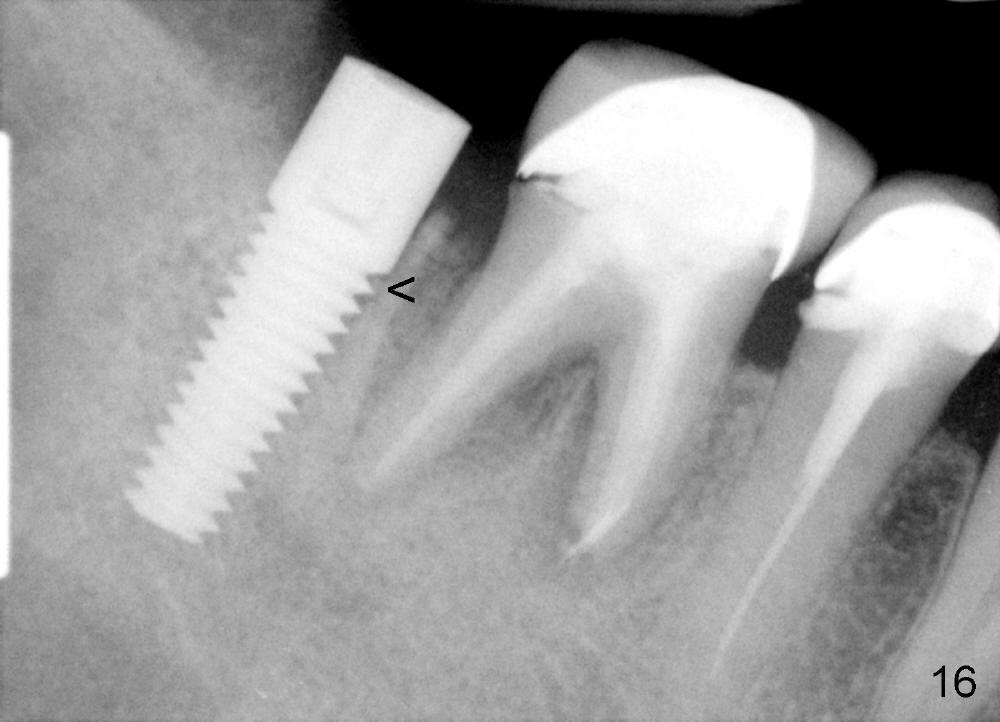

Four months postop, there is a sign of osteointegration (Fig.16 <). Graft particles migrate to the surface of the mucosa (Fig.17 <). A healing cuff is placed over the implant for preparation of restoration (Fig.18 H); graft particles are removed (<). Due to insurance issue, the restoration is yet to finish by 6 months postop (Fig.19 C: healing cuff); the cystic lesion appears to have been decreased concentrically (*). The bone density in the former cyst area continues to increase 14 and 32 months postop (Fig.20 A: abutment; Fig.22). Small piece of bone graft (<) is being extruded distobuccal to the #31 crown (C) asymptomatically 15 and 32 months postop (Fig.21,22).